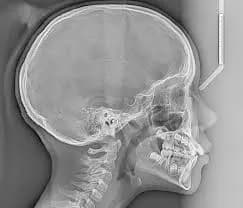

Essential lateral views providing crucial skeletal and soft tissue measurements.

An OPG (Orthopantomogram) is a single panoramic X-ray showing the teeth, jaws, and surrounding structures—commonly used in dental and emergency settings for quick, broad diagnosis. A Lateral Cephalogram (Lat Ceph) is a side-view X-ray of the face used to measure jaw alignment and bite, especially for orthodontic planning.

Supports overjet, overbite, skeletal class, and airway analysis